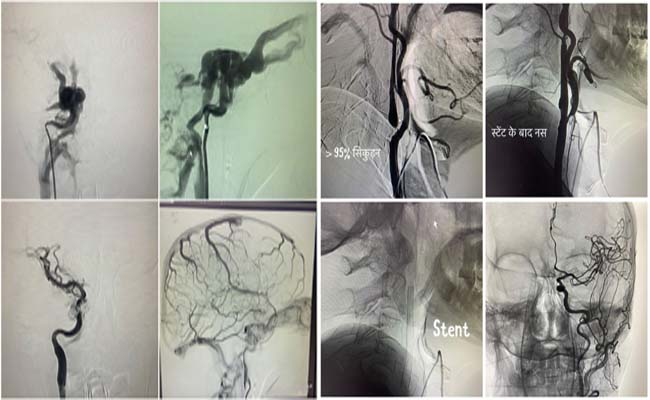

Aims Rishikesh : ऋषिकेश। अखिल भारतीय आयुर्विज्ञान में उच्च तकनीकी वाले न्यूरो इंटरवेंशन कैरोटिड स्टेंटिंग (खून की नस में सिकुड़न) ए.वी.एम व ए.वी.एफ (खून की नसों का गुच्छा), स्ट्रोक (लकवा), एन्यूरिजम (खून की नसों का गुब्बारा व नसों का फटना) समेत कई अन्य तरह की बीमारियों का बिना किसी चीरफाड़ के इलाज संभव है।

डॉ. चारण के मुताबिक इस विधि के तहत जांघ की खून की नस में 2 एमएम का पाइप डालकर ब्रेन तक पहुंच बनाई जाती है। उसके बाद बीमारी का बिना चीरफाड़ किए इलाज किया जाता है। बताया कि चूंकि इस उपचार में चीरफाड़ नहीं किया जाता है, लिहाजा मरीज को अस्पताल अथवा आईसीयू में निहायत कम समय तक ही रुकना पड़ता है।